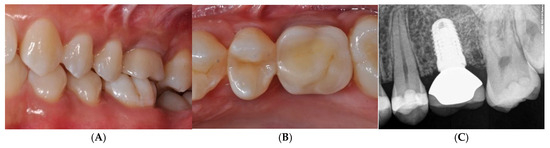

After implant insertion (Figure 7D), a healing abutment was immediately connected (Figure 7E) for transmucosal healing, avoiding additional surgery. After a 2-month healing time (Figure 7F), a provisional restoration was applied for progressive loading. At 6 months after implant insertion, a definitive porcelain-fused-to-metal crown was cemented (Figure 8A–C).

Provisional restoration was applied for progressive loading. At 6 months after implant insertion, a definitive porcelain-fused-to-metal crown was cemented (A–C).

This GBR procedure was effective for the reconstruction of the horizontal defect, and the bone underneath the TR-dPTFE membrane appeared well mineralized after a healing period of 10 months. The implant was inserted in well-matured and vascularized bone and achieved primary stability very easily. No additional ridge augmentation was required for implant placement. Regenerated bone was found to be uniform across the defect and was hard and well integrated. The patient was very satisfied with the aesthetic result of the prosthetic rehabilitation and the improved masticatory function. She was monitored at least twice a year, when she returned for professional hygiene sessions. There were no problems of peri-implantitis, unscrewing of the implant abutment screw or soft tissue recession. The 5-year clinical and radiographic follow-up after functional prosthetic loading showed the augmented hard and soft tissues well maintained, with no marginal bone loss around the implant and a bone density within the limits (Figure 9A,B).

5-year clinical (A) and radiographic (B) follow-up after functional prosthetic loading showed augmented hard and soft tissues, which were well maintained.